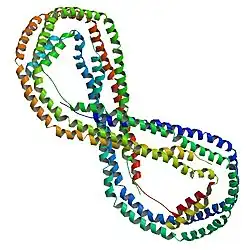

Structure

APOA1 is located on chromosome 11, with its specific location being 11q23-q24. The gene contains 4 exons.[7] The encoded apolipoprotein AI, is a 28.1 kDa protein composed of 243 amino acids; 21 peptides have been observed through mass spectrometry data.[8][9] Due to alternative splicing, there exists multiple transcript variants of APOA1, including at least one which encodes a Apo-AI preprotein.[7]